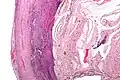

Pathology diagnosis of appendicitis can be made by detecting a neutrophilic infiltrate of the muscularis propria.

Micrograph of appendicitis and periappendicitis. H&E stain.

Acute suppurative appendicitis with perforation (at right). H&E stain.